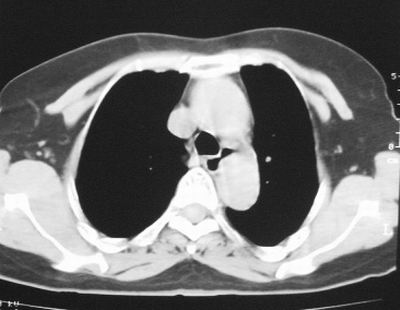

左下肺软组织块影,有分叶、毛刺、空泡及胸膜牵拉征,左下肺周围性肺癌。

左肺下叶周围型肺癌,支持!(软组织肿块+分叶+毛刺+空泡+胸膜凹陷征)

左下肺软组织密度影,可见分叶,边缘可见毛刺征,胸膜增厚,强烈要求左下肺周围型肺癌

左下肺后基底段实性肿块,周围有毛刺,病变周围有肺气肿,与降主动脉间有条带状影相连,病灶4年前查体发现,纵隔内未见肿大淋巴结。考虑.肺隔离症,建议增强扫描与周围型肺癌鉴别。